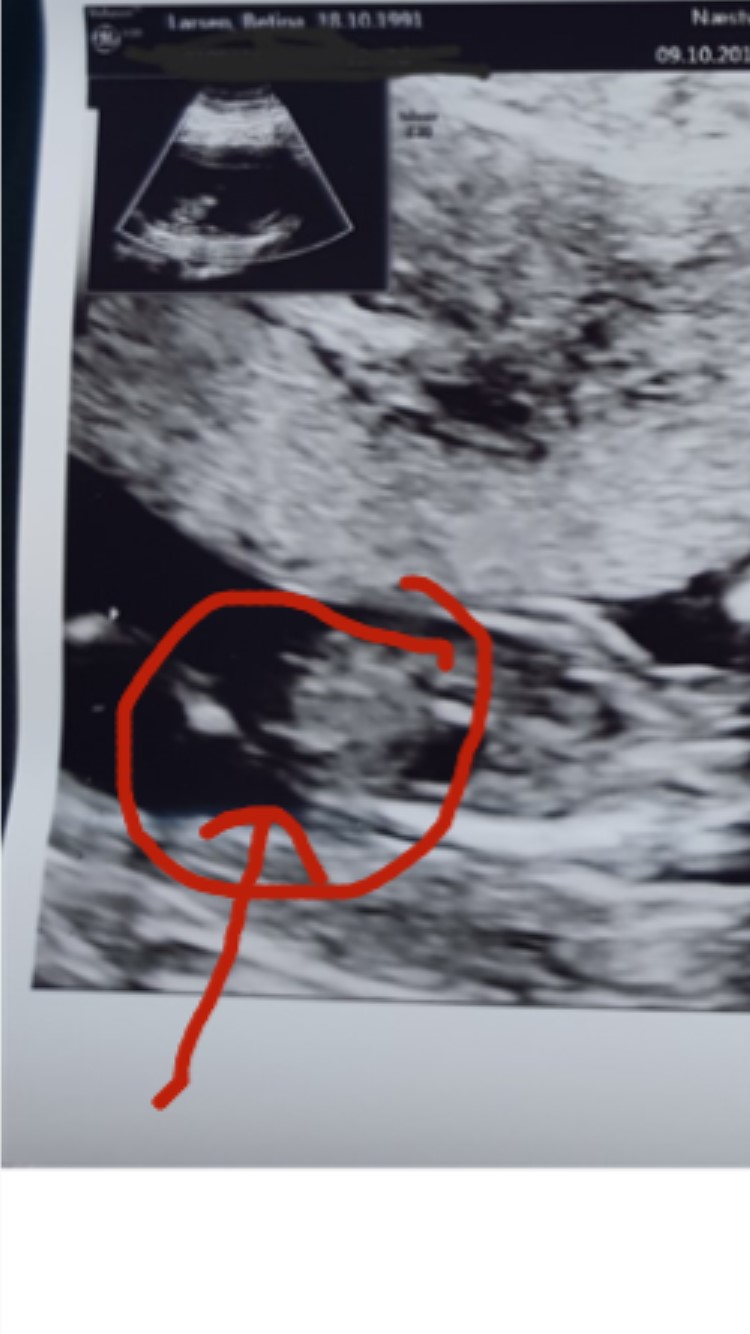

Har lige kopieret dit billede og sat en pil hvor nubben er.

Vedhæftede fotos (klik for at se i fuld størrelse)

tusind tak så kan jeg godt se det, hvor er det spændene